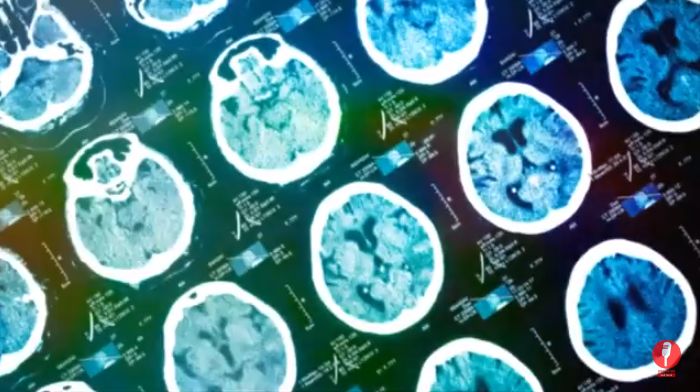

检测脑出血

以色列医疗技术公司MedyMatch和IBM Watson Health正在使用人工智能,通过检测颅内出血,帮助医院急诊室的医生更有效地治疗中风和头部外伤患者。AI系统使用临床洞察力(clinical insight)、深度学习、患者数据和机器视觉来自动标记潜在的脑出血,以供医生检查。